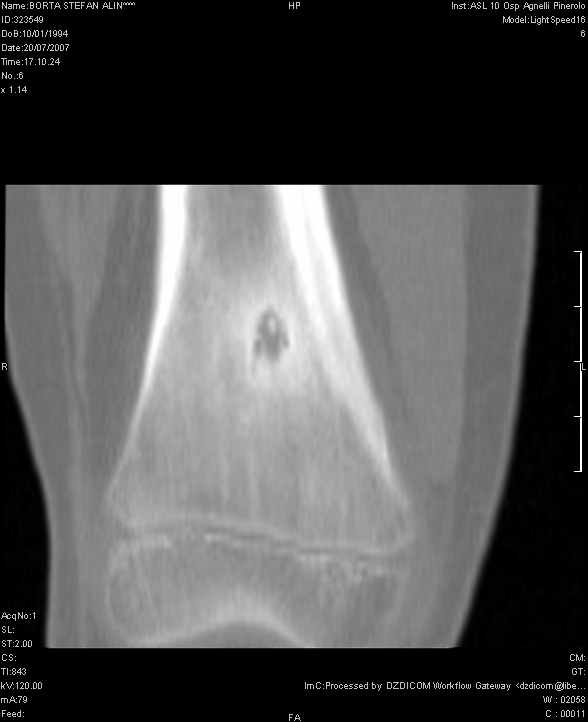

S. veniva dunque ricoverato presso il nostro Reparto di Pediatria. Gli esami di laboratorio inizialmente eseguiti erano normali e la radiografia del ginocchio non evidenziava anomalie. Veniva eseguita una TAC dell'arto inferiore dx che evidenziava una lesione di circa 5 mm di diametro a livello della corticale del femore distale, compatibile con OO (Figura 1). In seguito la scintigrafia total-body con Tecnezio-99 dimostrava una intensa captazione del tracciante a livello della diafisi distale del femore destro, con segni di ipervascolarizzazione e di aumentata attivit� osteoblastica. Per meglio definire la lesione veniva eseguita anche una Risonanza magnetica Nucleare (RMN) che confermava la presenza di un quadro compatibile con OO (Figura 2).

L'OO � il pi� comune tumore osseo benigno la cui storia naturale varia in base alla sede di presentazione; sono descritti casi di regressione spontanea dopo un periodo medio di 3-7 anni6. La TAC con mezzo di contrasto rappresenta la miglior tecnica di �imaging� per la diagnosi di OO in quanto frequentemente l'indagine radiologica standard risulta negativa come nel caso descritto.

La lesione alla TAC � piuttosto caratteristica: l'aspetto tipico di un'immagine lacunare osteolitica di piccole dimensioni circondata da una reazione sclerotica iperdensa � quasi sempre dirimente. Per la diagnosi differenziale (soprattutto con tumori ossei e istiocitosi) � utile l'esecuzione della scintigrafia ossea con Tecnezio-99 e della RMN, che pu� evidenziare la diffusione ai tessuti molli e l'eventuale coinvolgimento intramidollare (in caso di lesioni a localizzazione vertebrale).

Figura 1. La TC del femore dx dimostra la presenza in sede iuxtametafisaria di addensamento della trabecolatura ossea che circoscrive un'area di maggior radiotrasparenza.